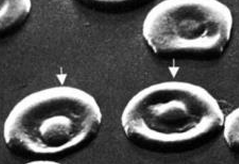

Feline Reticulocytes์ ์ข ๋ฅ

- ๊ฐ์๋ ๋ฌ๋ฆฌ, ๊ณ ์์ด์์ NMB staining์ ํ๋ฉด 2๊ฐ์ง ํํ๋ก ๊ด์ฐฐ๋๋ค.

- (1) Punctate type : reticulum ์ ์ (2-6๊ฐ ์ ๋)

- (2) Aggregate type : reticulum์ด ํจ์ฌ ๋ง์, ๊ณจ์์์ ๋ฐฉ์ถ๋ ์ง ์ผ๋ง ์ ๋จ

- ์ผ์ชฝ : NMB staining๋ก ํ์คํ๊ฒ ๊ตฌ๋ถํ ์ ์๋ค. (A=aggregate form, P=punctate form)

- ์ค๋ฅธ์ชฝ : Diff-quik staining์์๋ ํต ์์ฌ๋ฌผ์ด ๋จ์ ์๋ polychromatophilic RBC์ ํํ๋ก ๊ด์ฐฐ๋๋ค.